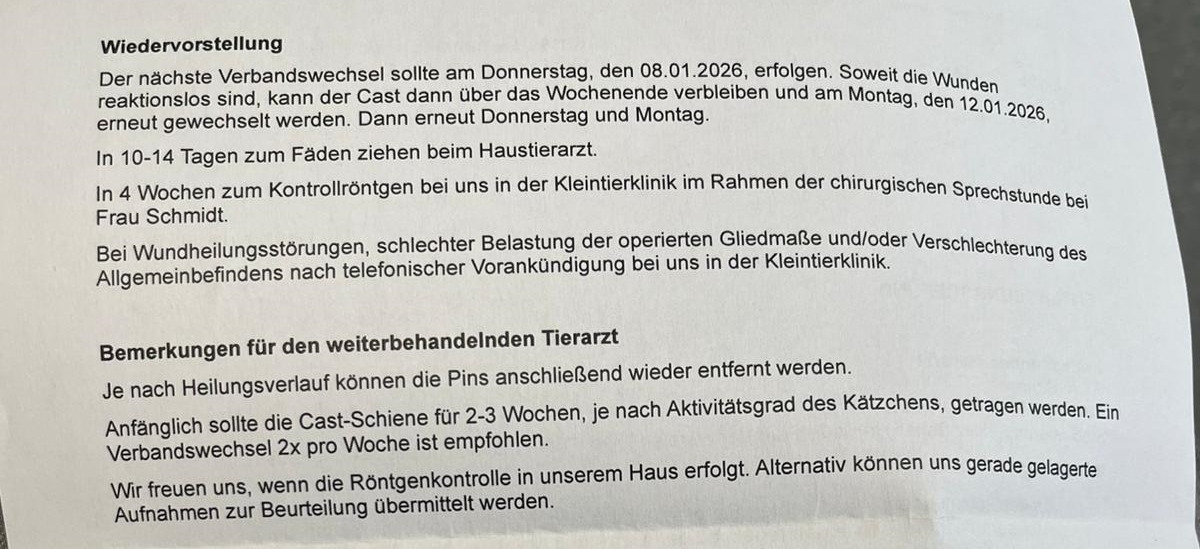

Wendy wurde umgehend in die Tierklinik Leipzig überwiesen und dort operiert. Das Bein wurde mittels Pins stabilisiert und zusätzlich eingegipst. Die Operation war aufwendig, aber notwendig, um ihr Bein und ihre Zukunft zu retten.

• 4 Wochen strikte Boxenruhe

• Verbandswechsel 2× pro Woche

• in 4 Wochen Kontrollröntgen

• eventuell müssen die eingesetzten Pins später erneut operativ entfernt werden

Es werden also weitere Tierarztkosten auf uns zukommen.